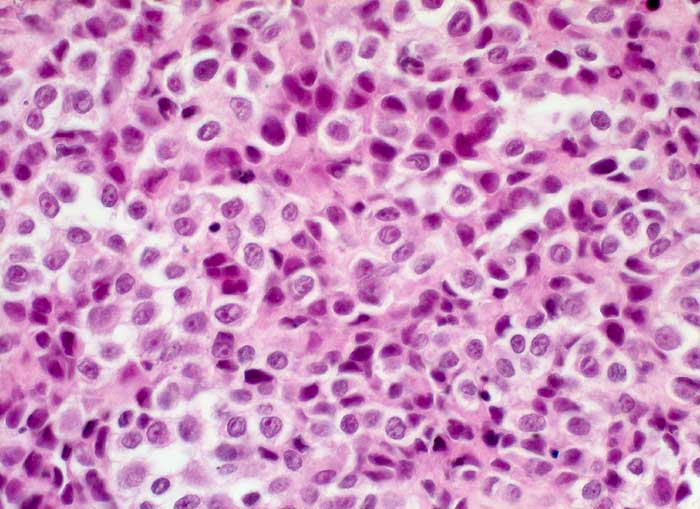

l/ Maligner Pleuraerguss: Malignes Melanom

Maligner Pleuraerguss: Malignes Melanom

Der Nachweis von eisennegativem Pigment und die Positivität für den melanozytären Marker HMB-45 in malignen Zellen bestätigt die Diagnose eines malignen Melanoms.